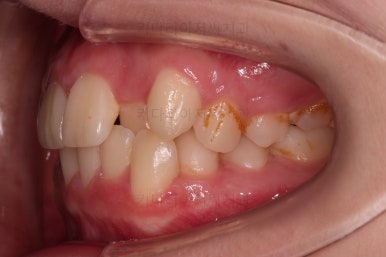

장치를 처음 부착한 사진입니다.

이번 환자분은 특징적으로 윗니의 장치와 아랫니의 장치가 다르죠.

윗니는 좀 더 심미적인 세라믹으로 선택하셨고 아랫니는 비교적 저렴하고 부피가 약간 작고 튼튼한 메탈로 진행했습니다.

그래도 됩니다.

심지어는 같은 회사 제품이 아니더라도 적절하게 세팅을 고려하면 섞어 사용하는 것도 가능하답니다.